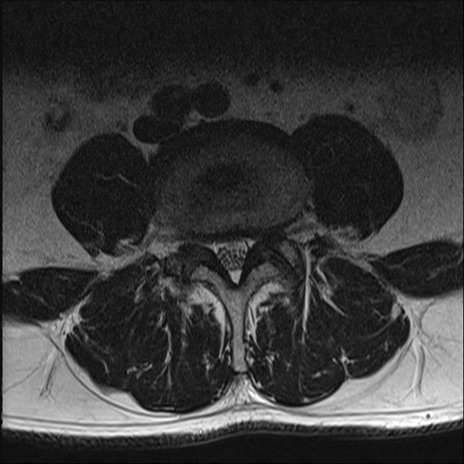

【整形】TIPS症例2 腰椎MRI T2WI(横断像)

【症例】70歳代男性

【主訴】左下肢痛

【現病歴】2週間前くらいから腰痛、左下肢痛あり。左臀部から大腿、下腿外側のしびれが常時ある。歩行とともに同部位の痛みあり。

【身体所見】Lasegue70-/60+、Bragard-/±、PTR ±/±、ATR -/-、IP 5/5、TA 5/4、TS 5/5、EHL 右第1足趾なし/3、FHL 5/5、hypersthesia(-)、足背動脈触知良好

異常所見と診断は?